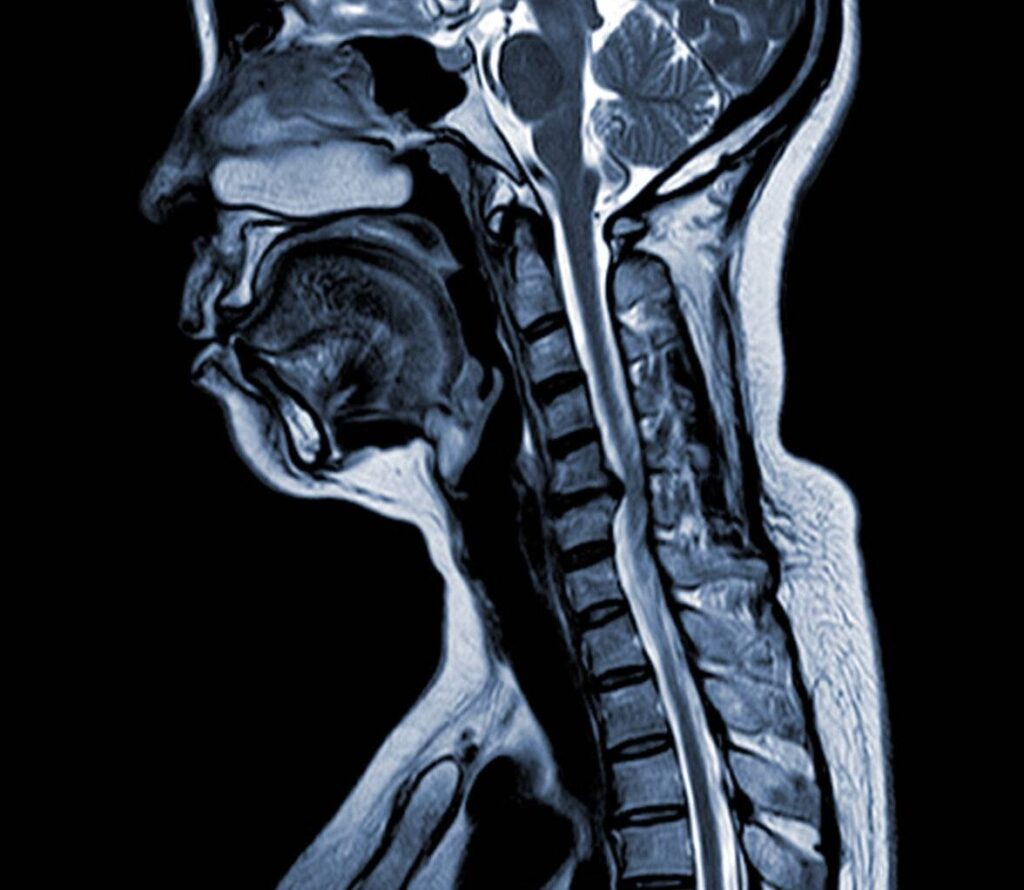

Die MRT hingegen nutzt starke Magnetfelder und Radiowellen, um detaillierte Bilder von Weichteilen wie Rückenmark, Bandscheiben und Nerven zu liefern. Die Entscheidung für eine der beiden Methoden hängt vom klinischen Kontext und den spezifischen diagnostischen Anforderungen ab.

CT Bilder Wirbelsäule

Die Wirbelsäule ist eine komplexe Struktur mit zahlreichen Knochen, Bandscheiben, Bändern und Nerven. Die CT-Bildgebung der Wirbelsäule kann diese komplizierte Anatomie mit außergewöhnlicher Klarheit erfassen. Diese Detailgenauigkeit ist für die Diagnose zahlreicher Erkrankungen wie Frakturen, degenerative Veränderungen, Spinalkanalstenose und Tumore unerlässlich. Darüber hinaus können CT-Bilder dazu beitragen, die Ursache von Rückenschmerzen oder neurologischen Symptomen zu ermitteln, indem sie Probleme sichtbar machen, die auf Röntgenbildern möglicherweise nicht zu erkennen sind.